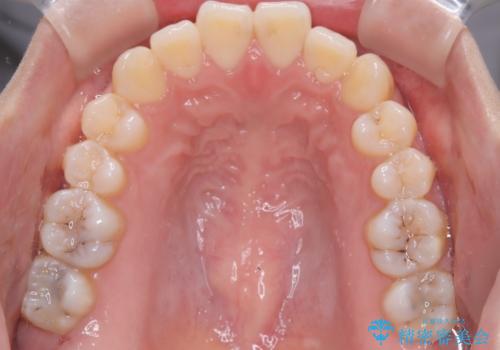

【ワイヤー矯正】前歯の突出感、下の歯の並びを良くしたい

- 主訴:上の前歯の突出感と下の歯の並びを改善したい

非抜歯で矯正治療を行った場合と、上下左右4番目の歯を抜歯して矯正治療を行った場合のシミュレーションを見ていただき、非抜歯での矯正治療を希望されました。

非抜歯にて矯正治療を行いました。

IPRを行い、前歯部の突出感の改善に努めました。

期間:1年9カ月